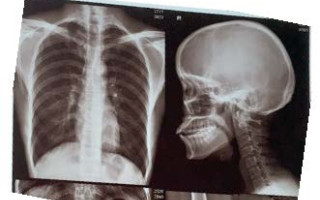

- تفسیر فیلم رادیوگرافی با استفاده از هوش مصنوعی و روش های پردازش تصویر.